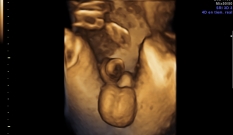

Se a gravidez for de baixo risco, após a 40ª semana costuma-se monitorar o feto por meio de cardiotocografia (NST - NonStress Test), que consiste na colocação de fitas e sensores no abdômen que são conectados a um monitor que registra a frequência cardíaca do feto (normalmente entre 120-160 batimentos por minuto) e as contrações da mulher grávida.

Este é um teste para avaliar o bem-estar fetal que também pode ser realizado em qualquer outro momento do terceiro trimestre se a paciente for ao pronto-socorro relatando contrações.